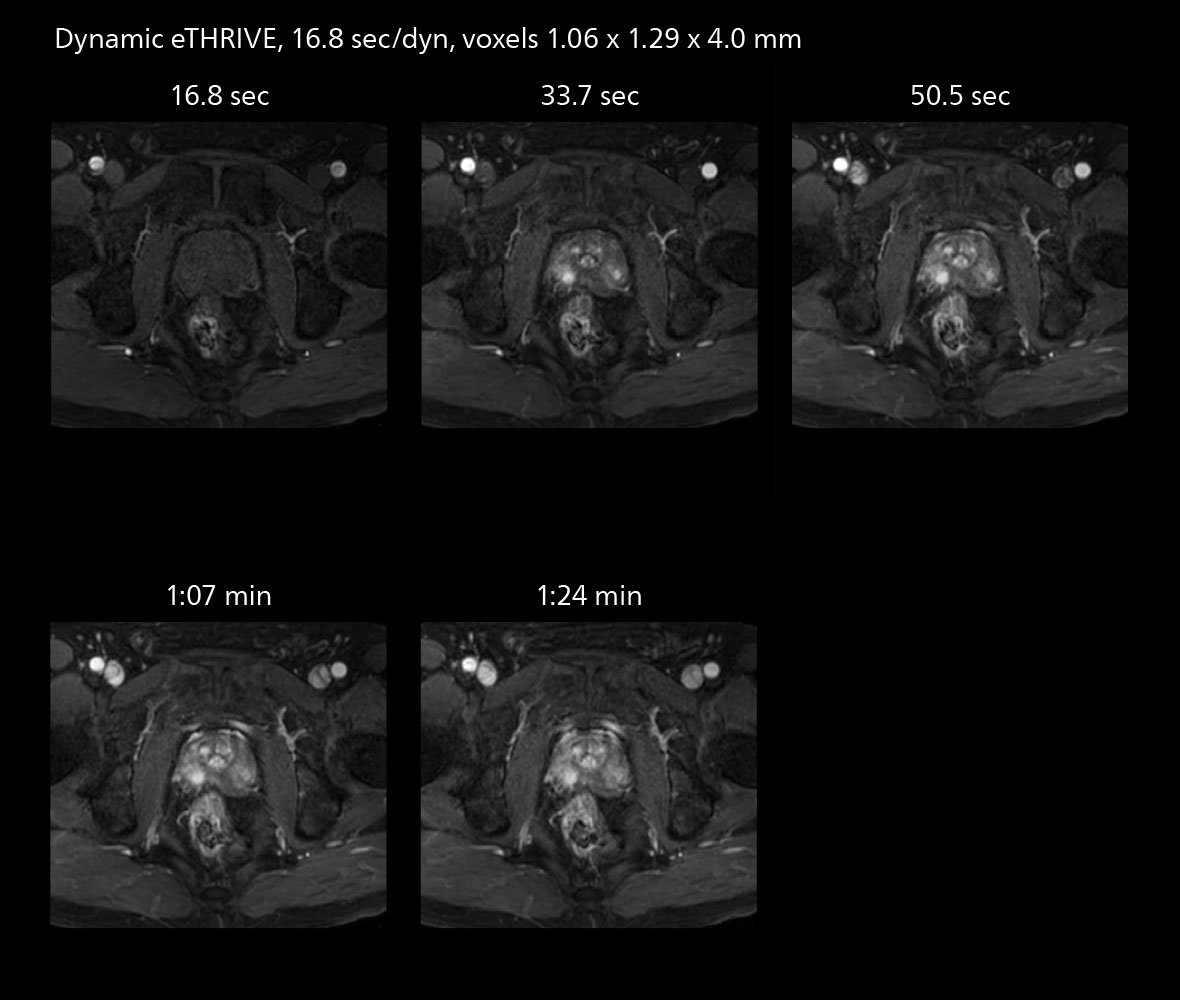

Diffusion studies benefit from powerful gradients

The high performance of the Vega HP gradients is particularly impressive in DWI. “The Vega HP gradients enable us to scan faster and use b-values as high as 2000, for example in prostate DWI and in DWIBS, which provides image quality that is remarkably improved over the previous system and we are able to more easily see lesions.”

The value of the Elition X gradients is also evident in DWIBS studies. “The fact that we can consistently obtain distortion‐free DWIBS while reducing imaging time at three coronal stations is excellent,” Dr. Makuuchi says. “In these patients, it’s also important that the application of Compressed SENSE to T2‐weighted, STIR and mDIXON sequences has no impact on the examination time of whole‐body imaging. As a result of the increased speed and higher image quality we realize, DWIBS studies have now become routine examinations.”

Fast whole body DWIBS examination

With SmartPath to Elition X the team can obtain excellent quality DWIBS imaging and reduce imaging time. Other sequences also fit in the examination slot. This case shows left paravertebral neurogenic tumor and Th10 vertebral hemangiomas.

Fast whole body DWIBS examination

With SmartPath to Elition X the team can obtain excellent quality DWIBS imaging and reduce imaging time. Other sequences also fit in the examination slot. This case shows left paravertebral neurogenic tumor and Th10 vertebral hemangiomas.